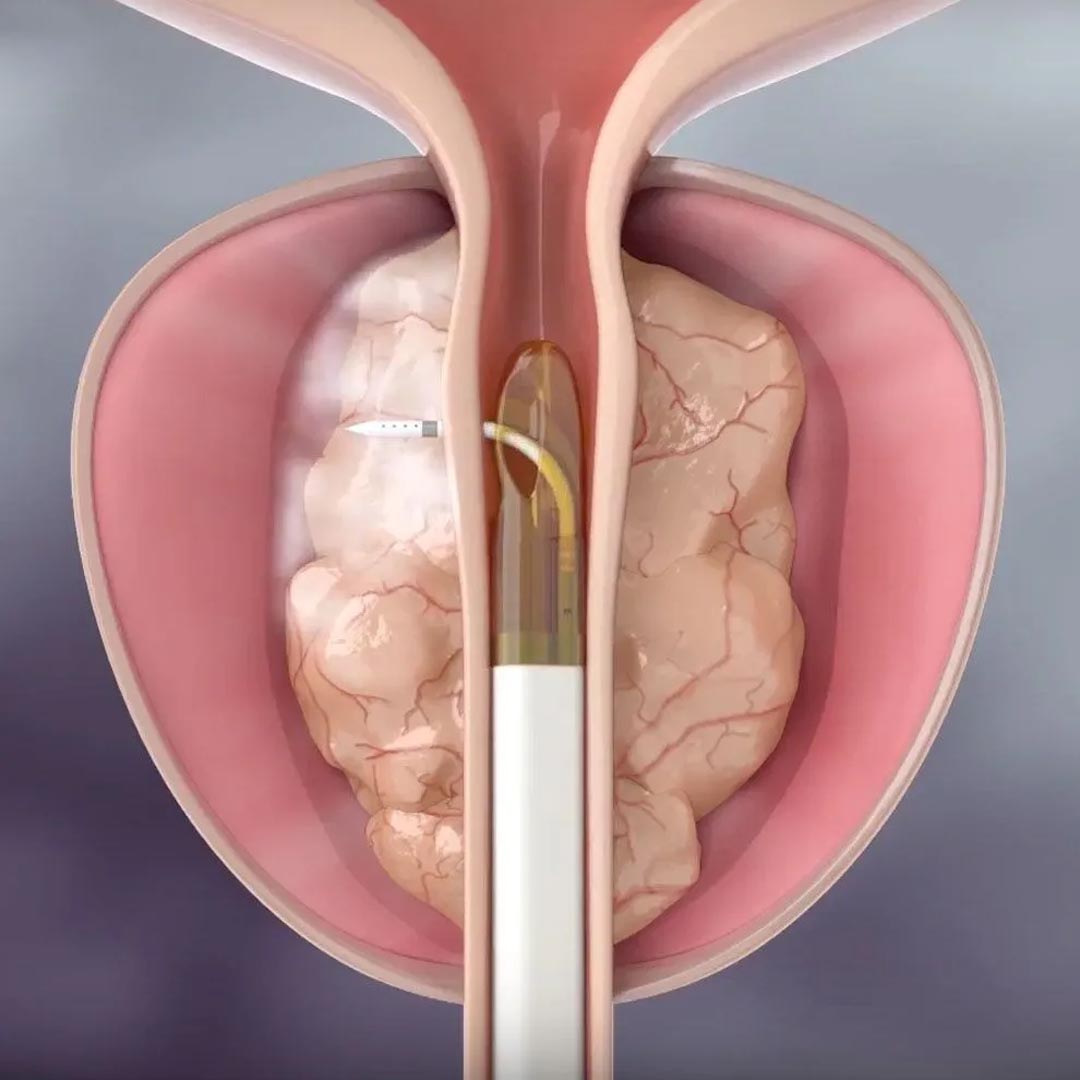

TPLA - Terapia Termica Laser Percutanea Ecoguidata

Innovativa tecnica percutanea sotto guida ecografica. Esegue una necrosi controllata della porzione centrale della prostata. Indicato per prostate anche voluminose. Non necessita di resezione né cateterismo prolungato.